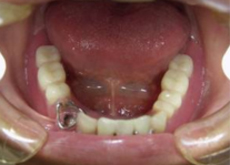

下顎がインプラント用フルデンチャーにかわりました。 | |

| 上顎正中の歯がずいぶん大きく挺出しています。 審美的にも良くないので設計をインプラント用フルデンチャーに変更します。

上顎4・4にインプラント体を埋入しました。右1番左2番はデンチャー完成時に歯冠を削合します。 |